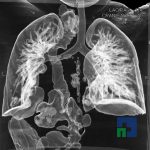

Examinare de rutină cerebrală, nativ și cu substanță de contrast (SDC) pentru diagnosticul:

- Accidentelor vasculare cerebrale ischemice sau hemoragice

- Tumorilor cerebrale